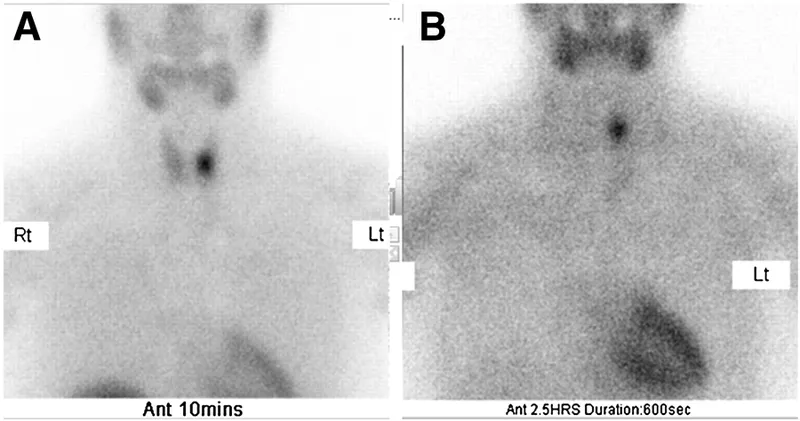

Next, pre-operative localization is key for planning minimally invasive surgery. The typical imaging workflow is:

- Pre-op localization with Sestamibi scan and ultrasound enables minimally invasive parathyroidectomy.